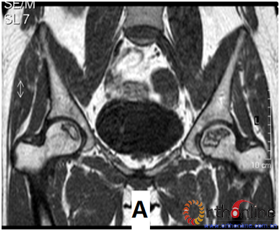

图2 依据股骨头外侧柱存留情况,股骨头坏死的分型。(图2-1)分为Ⅰ型(外侧柱全部存留)(A)MRI图像显示;(B)7年后CT显示股骨头仍未塌陷;(图2-2)Ⅱ型(外侧柱部分保留)(A)MRI显示外侧皮质存留;(B)4年后CT显示股骨头仍未塌陷;(图2-3)Ⅲ型(坏死带穿透股骨头);(A)MRI显示坏死带;(B)2年后股骨头塌陷

Fig 2 According to preservation of the lateral pillar, the necrosis was divided into three types. (Fig 2-1)Type Ⅰ: Whole lateral pillar preserved (A) MRI showing; (B) no collapse occurred seven years later by CT showing. (Fig 2-2)Type Ⅱ: Preservation of the partial lateral pillar, (A) MRI showed the preservation of the lateral cortical bone; (B) no collapse of the femoral head four years by CT. (Fig 2-3)Type Ⅲ: the necrotic line pass through the cortical bone and bone morrow ;(A) MRI showed the necrotic line; (B) collapse of the femoral head occurred two year later.